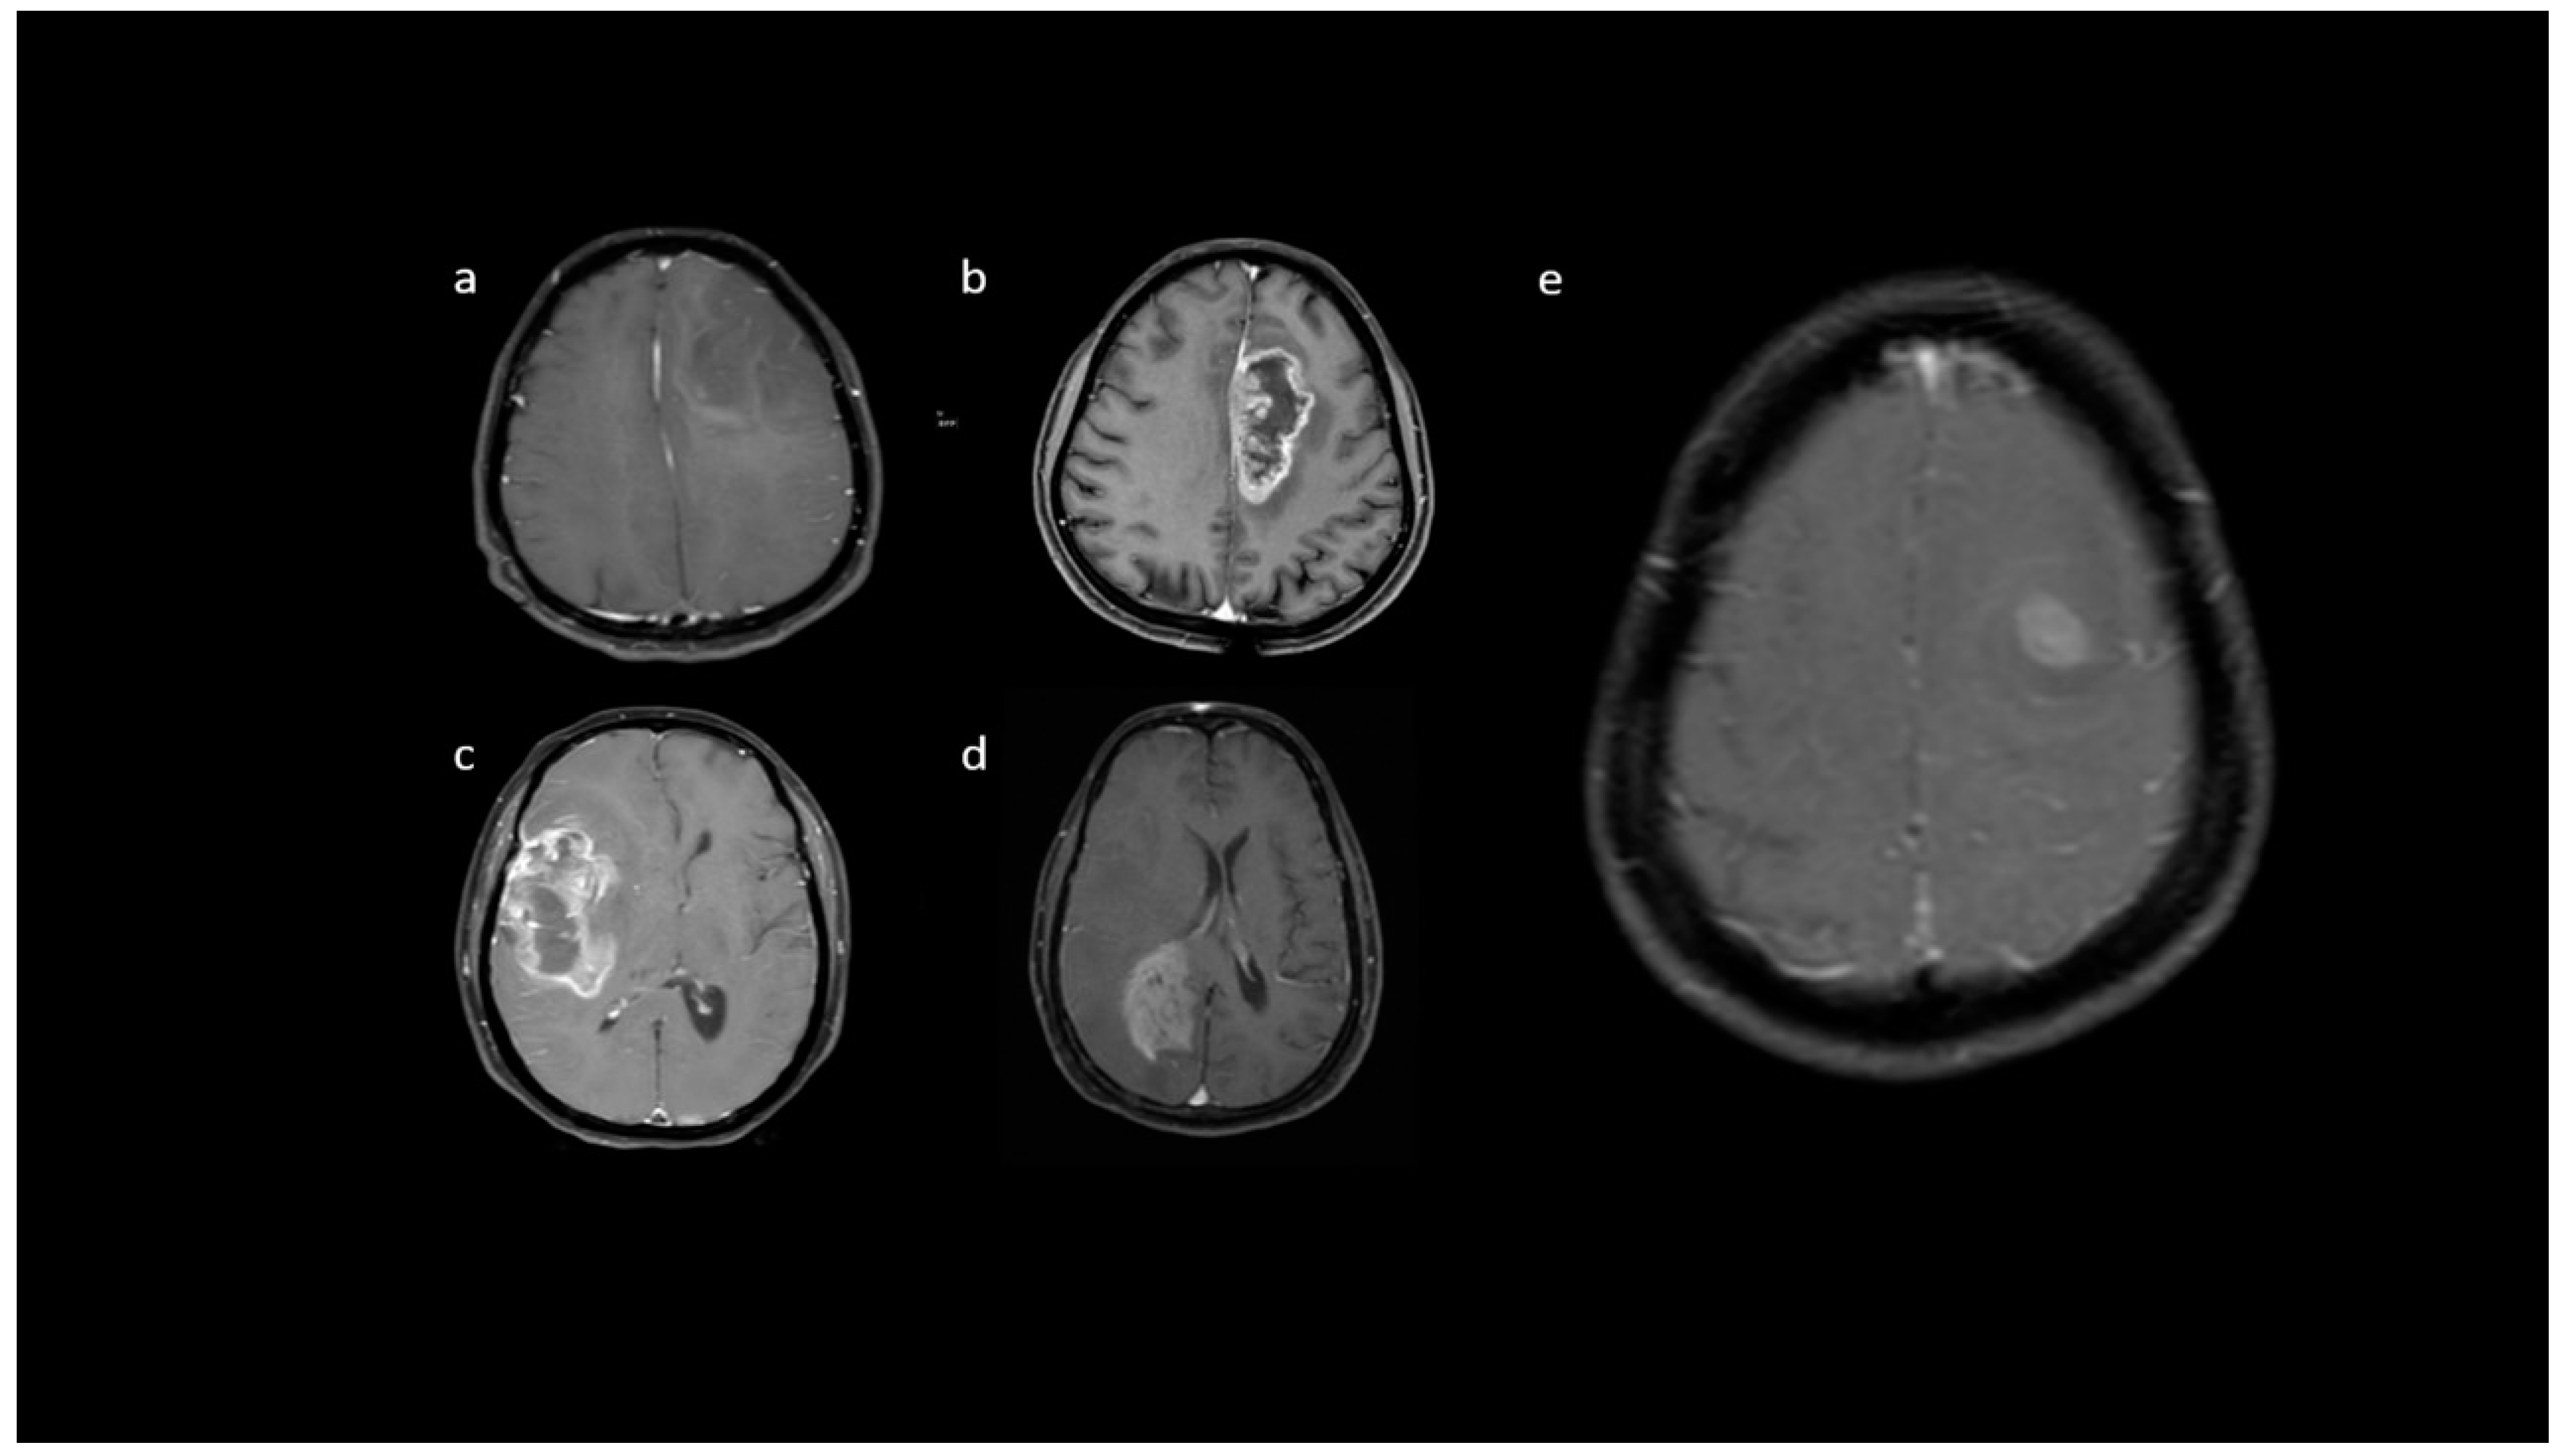

| Variable | Parameter | IDH-Mutated (n = 19) | IDH-Wildtype (n = 129) | p-Value |

|---|---|---|---|---|

| Enhancement I | Mild | 9 (47.4) | 5 (3.9) | <0.001 |

| Moderate | 6 (31.6) | 25 (19.4) | ||

| Severe | 4 (21.1) | 99 (76.7) | ||

| Enhancement III | Rim | 6 (31.6) | 104 (80.6) | <0.001 |

| Nodular | 0 | 2 (1.6) | ||

| Patchy | 11 (57.9) | 13 (10.1) | ||

| Solid | 2 (10.5) | 10 (7.8) | ||

| Necrosis | None | 3 (15.8) | 3 (2.3) | <0.001 |

| <25% | 11 (57.9) | 14 (10.9) | ||

| 25- 50% | 2 (10.5) | 35 (27.1) | ||

| >50% | 3 (15.8) | 77 (59.7) | ||

| Dural enhancement | AbsentPresent | 07 (70.0) | 31 (24.0)48 (52.7) | 0.013 |

| Edema | None | 3 (15.8) | 3 (2.3) | 0.025 |

| <tumor volume | 11 (57.9) | 68 (52.7) | ||

| Equal to tumor volume | 4 (21.1) | 35 (27.1) | ||

| >tumor volume | 1 (5.3) | 23 (17.8) | ||

| Cysts * | No | 11 (57.9) | 115 (89.1) | 0.001 |

| Yes | 6 (31.6) | 14 (10.9) | ||

| Subcortical involvement | Involved | 18 (94.7) | 94 (72.9) | 0.044 |

| Not involved | 1 (5.3) | 35 (27.1) | ||

| rCBV | Median (IQR) | 1.8 [1.4–2.0] | 2.6 [1.9–3.5] | 0.001 |